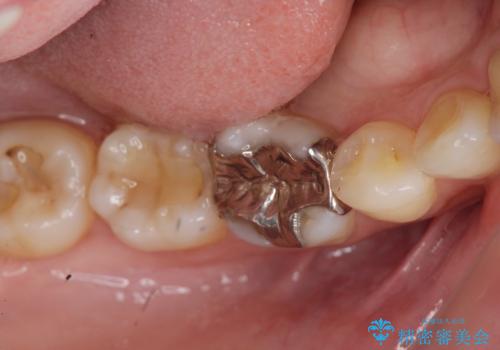

- 笑った際に見える銀歯を白くしたいと希望され来院されました。

銀歯の周囲にも虫歯が見られたのでインレーではなく、耐久性の強いフルジルコニアクラウンでの治療を計画します。